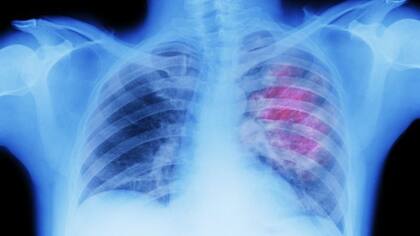

Reliquias de virus antiguos -que pasaron millones de años escondidos dentro del ADN humano- ayudan a nuestro cuerpo a combatir el cáncer, según señala un estudio llevado a cabo por investigadores del Instituto Francis Crick, en Reino Unido.

La investigación mostró que los restos latentes de estos viejos virus se despiertan cuando las células cancerosas se salen de control.

Y esto ayuda involuntariamente al sistema inmunitario a atacar el tumor. El equipo quiere ahora aprovechar este descubrimiento para diseñar vacunas que puedan potenciar el tratamiento contra el cáncer, o incluso prevenirlo.

Los investigadores habían notado un vínculo entre una mejor supervivencia frente al cáncer de pulmón y una parte del sistema inmunológico, llamadas células B, que se agrupan alrededor de los tumores.

Qué estaban haciendo exactamente en el cáncer de pulmón era un misterio, pero una serie de intrincados experimentos con muestras de pacientes y pruebas con animales demostraron que todavía estaban intentando combatir virus.